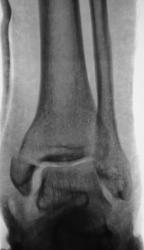

Дорогие друзья, может быть я чего- нибудь не понял, но такое впечатление, что после репозиции стало хуже, чем до неё( по видимому, смещение отломка внутренней лодыжкм кпереди стало более выраженное).

Целью репозиции в данном случае должно являться восстановление конгруэнтности в суставе. После репозиции суставная поверхность более-менее восстановлена. Конечно, идеальным в данном случае будет оперативное лечение. Но даже если оставить "всё как есть", все должно срастись в гипсе.

Произведена репозиция отломков и наложена гипсовая повязка.